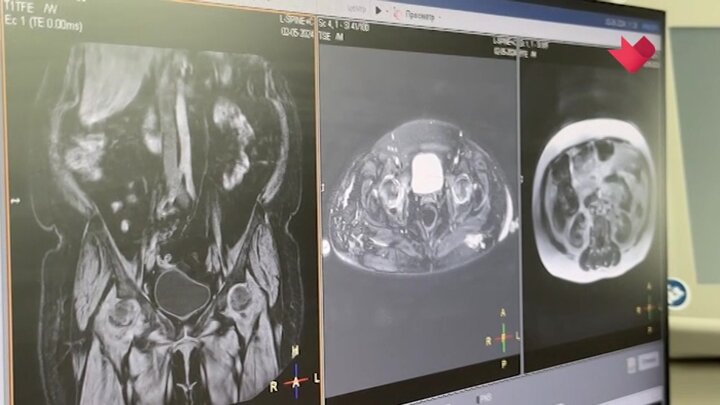

В столице создали уникальную методику лечения позвоночника. Ее внедрили в практику специалисты Московского спинального центра больницы имени Ворохобова. Теперь пациенты быстрее проходят реабилитацию и возвращаются к обычной жизни. Инновационное лечение уже прошли более 1 000 человек.